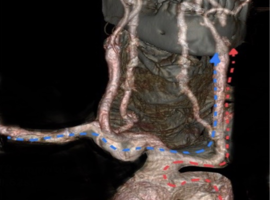

Clinical Cardiology Case Report

The Journal offers case reports in clinical cardiology, images, case series and heart surgery videos to publish. original research, research articles, review articles, case studies, commentaries, short communication, and Letters to the heart problem, heart and blood vessel disorders, cardiovascular diseases, myocardial infarction (heart attack), issues of cardiac arrest, stroke, techniques and procedure used in stent implantation, anticoagulant drugs (blood thinners), basic research in heart structure and functions and other medical conditions and associated treatments is aiming to stand out and publish remarkable findings in the major areas of cardiovascular medicine emphasizing on diagnostic, therapeutic and disease management sections.